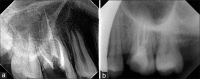

Inappropriate mechanical debridement, persistence of bacteria in the canals and apex, poor obturation quality, over and under extension of the root canal filling, and coronal leakage are some of the commonly attributable causes of failure. Despite the high success rate of endodontic treatment, failures do occur in a large number of cases and most of the times can be attributed to the already stated causes. With an ever increasing number of endodontic treatments being done each day, it has become imperative to avoid or minimize the most fundamental of reasons leading to endodontic failure. This paper reviews the most common causes of endodontic failure along with radiographic examples.